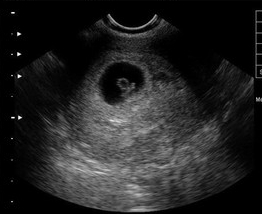

【NO.4】B超检查

[早孕结果]:同房后20天左右(医院检查,可信度高,结果准确,可判断是否为宫外孕)

方法点评:用B超诊断早孕是正确可靠的方法。在B型超声波屏上就可显示出子宫内有圆形的光环,又称妊娠环,环内的暗区为羊水,其中还可见有节律的胎心搏动,还可以看到孕囊大小、孕囊位置、还可以看到胎心和胚芽。

B超检查准吗?

医生指出,B超检查也能确定是宫外孕还是宫内妊娠,胚胎是否存活,这个是其他检查无法比拟的优点。